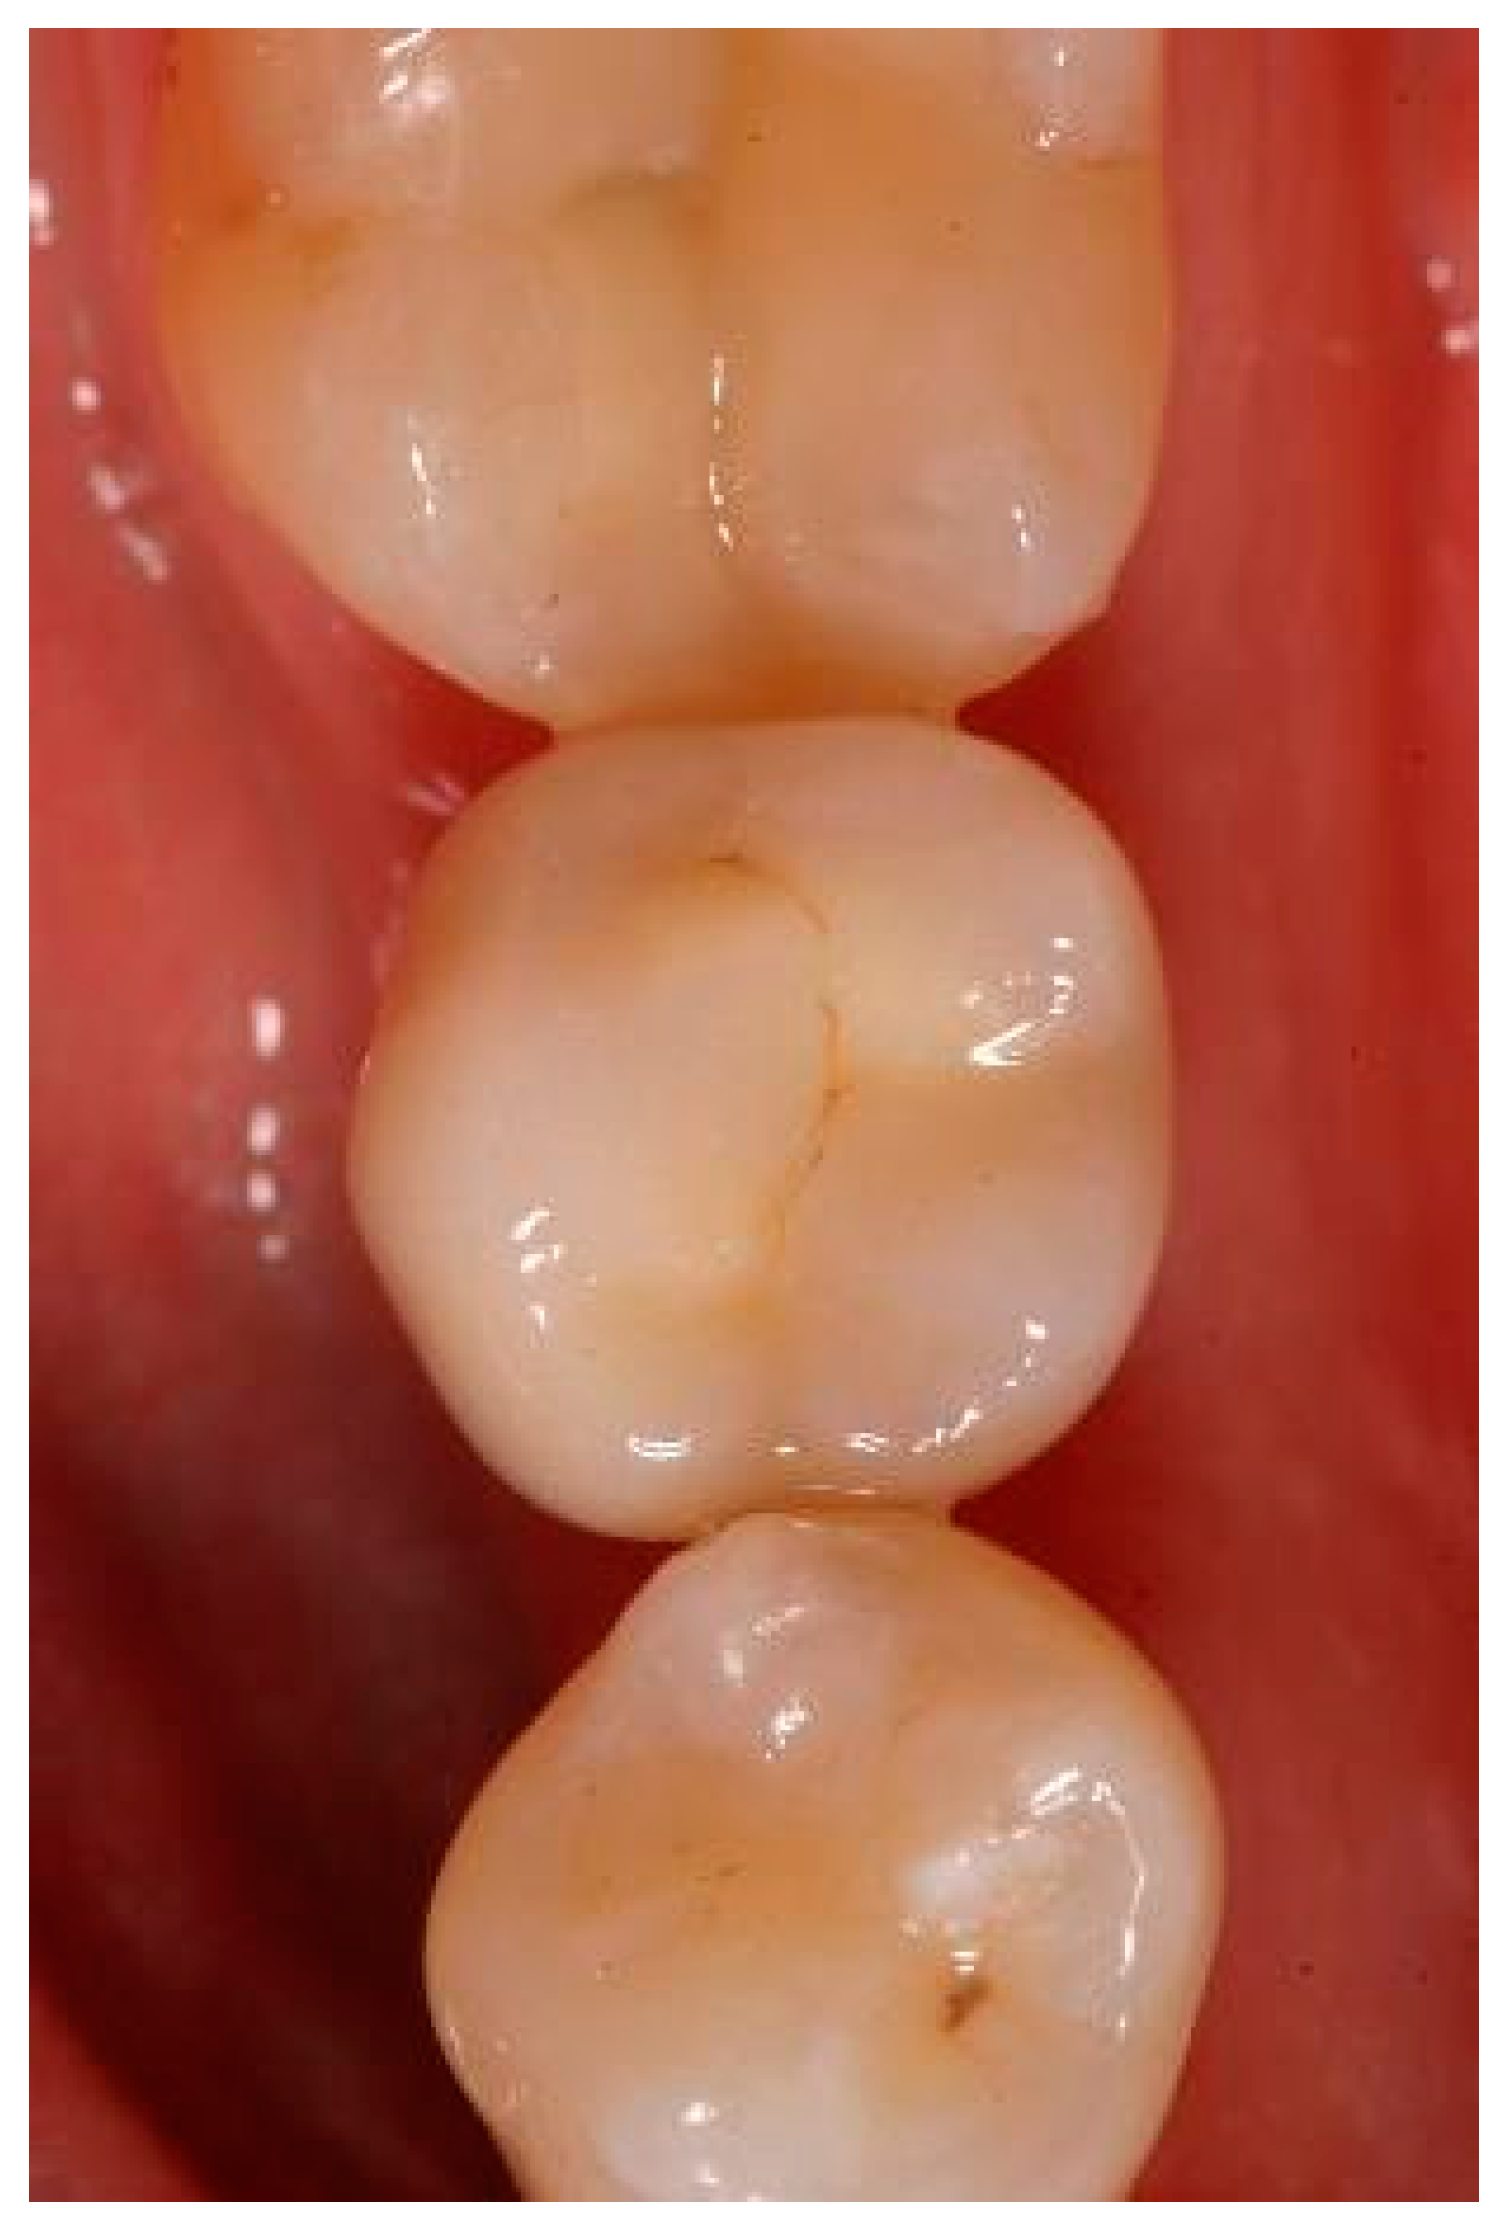

Appendix A. Exemplary Photographs and Radiographs from a Patient at Different Examination Time Points and a Positive Outcome